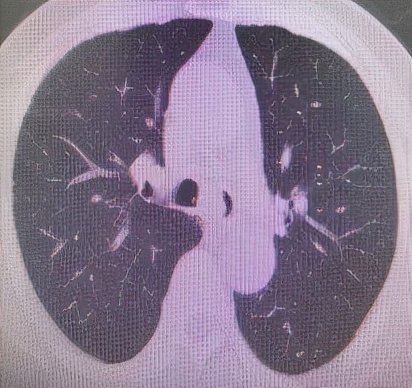

肺 部 C T (削瘤前)

于世寰主任介绍到,患者气管分叉处占位病变面积较大,已累及左、右主支气管,从肺CT影像上判断隆突区病变导致左主支气管狭窄约70-80%左右、右主支气管狭窄约50-60%左右,可操作空间十分有限,支气管镜介入治疗难度较大。隆突区占位病变已累及左右主支气管导致了呼吸困难已不适宜行外科手术治疗,必须通过支气管镜削瘤治疗来解除病人因气道梗阻导致的呼吸困难。支气管镜削瘤治疗与开胸外科手术相比,有痛苦小、创伤小、花费少、可重复性强、并发症少等优点。